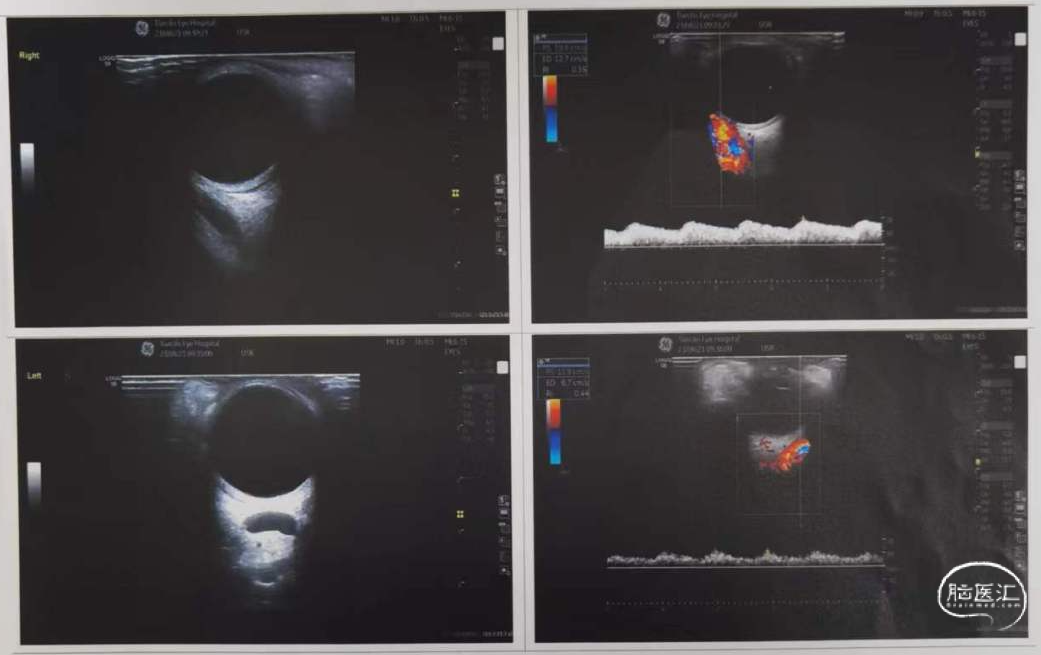

眼科检查提示双眼眼上静脉增粗。